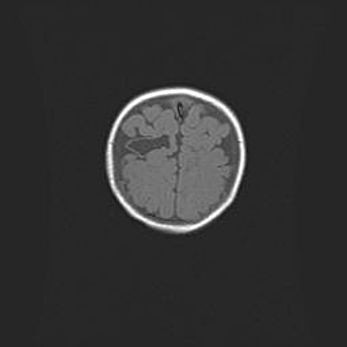

Сообщающаяся гидроцефалия. Кистозная энцефаломаляция головного мозга.

Возраст: 3 месяца 4 дня

Вес: 3100 г

Пол: женский

Окружность головы: 34 см

Срок гестации: 31 неделя

Кистозная энцефаломаляция головного мозга - одна из форм поражения головного мозга в детском возрасте. Характеризуется возникновением множественных и распространённых кист в коре, белом веществе и подкорковых образованиях головного мозга у плодов, новорождённых и детей раннего возраста. Развитие кистозной энцефаломаляции связано с внутриутробной асфиксией и гипотонией, родовой травмой, тромбозом синусов, пороками развития сосудов, инфекциями, сепсисом и другими причинами. Наиболее значимые инфекционные агенты: вирусы простого герпеса, цитомегалии, краснухи, токсоплазмы, энтеробактерии, золотистый стафилококк и другие.